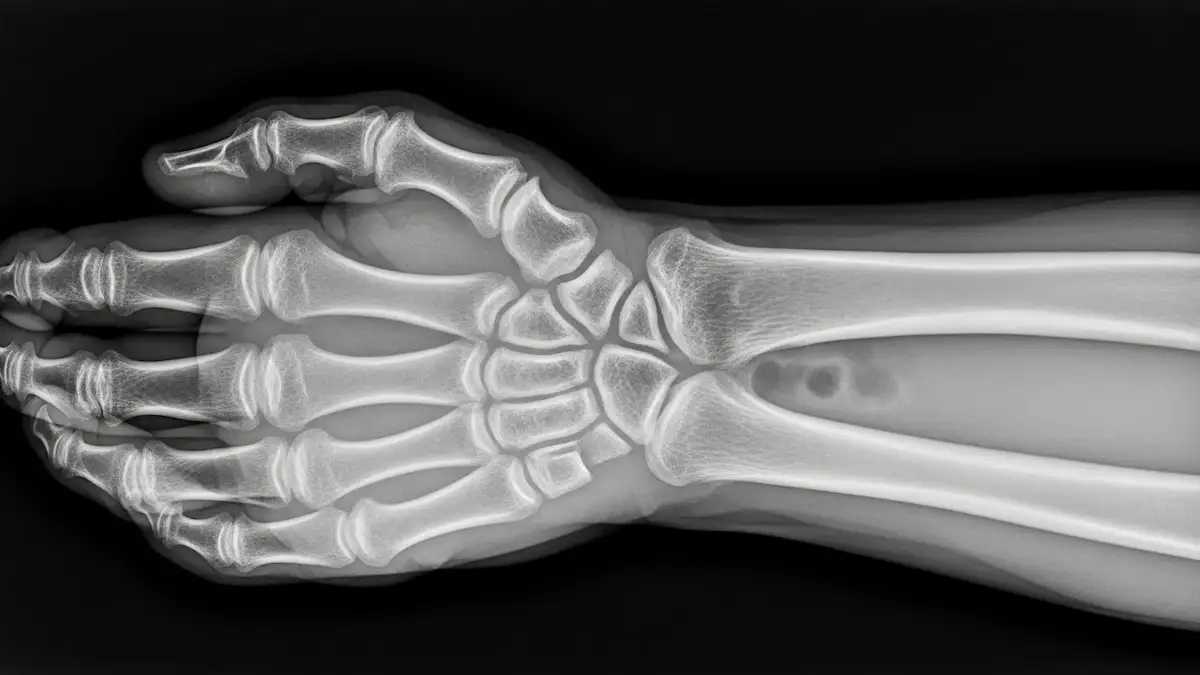

O diagnóstico da artrose do punho parte da avaliação clínica, considerando queixas de dor, sensação de rigidez e redução da mobilidade articular.

Exames de imagem, como radiografia, confirmam o desgaste articular, enquanto a ressonância magnética pode ser solicitada para avaliar cartilagem, ligamentos e estruturas associadas.

Na maioria dos casos, a radiografia identifica o desgaste articular e a presença de osteófitos.